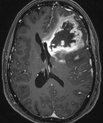

New technique to help brain cancer patients

Billedet er stillet til rådighed af afdelingslæge Anna Tietze, Aarhus Universitetshospital.

23 August 2013 - Health and disease

A new scanning technique developed by Danish and US researchers reveals how susceptible patients with aggressive brain cancer are to the drugs they…